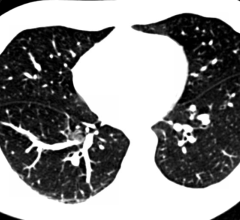

Previous evidence, including published National Lung Cancer Screening Trial (NLST) results, shows that computed…